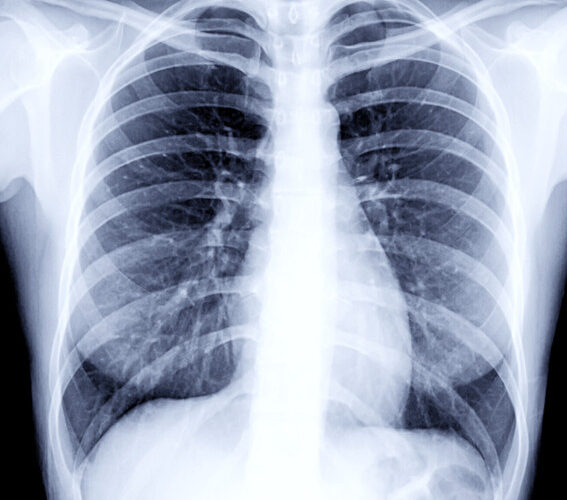

• TB सक्रिय भए (Active TB): तुरुन्त अस्वीकृत।

• पुरानो दाग भए (Inactive scar): थप परीक्षण (जस्तै sputum test) गर्न लगाइन्छ।

• यदि रिपोर्टमा रोग सक्रिय छैन भन्ने प्रमाण भए पनि कतिपय देशहरूले स्वीकार गर्दैनन्।

“Chest X-ray मा देखिने दाग सधैं सक्रिय रोगको संकेत होइन। धेरै पटक रोग पुरानो भएर निको भइसकेपछि पनि दाग देखिन्छ। तर वैदेशिक रोजगारमा स्वास्थ्य परीक्षण गर्ने संस्थाहरू अत्यन्तै कडाइ गर्छन्। उनीहरूले रोग सक्रिय छैन भनेर बुझ्दा पनि स्वीकार नगर्ने अवस्था हुन्छ।”